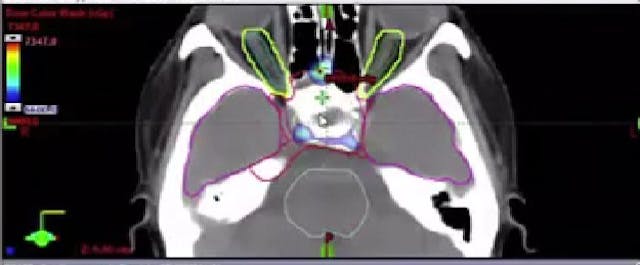

10/31/2025 - Dr. David Sher - Radiation Oncology - Head & Neck

Chartrounds US - Head and Neck Cancer • 56m